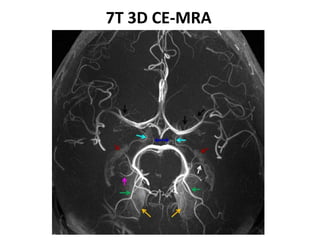

7T 3D CE-MRA

9- Light blue arrow

demonstrate-

1- Anterior choroidal artery

2- Posterior choroidal artery

3-PCOM

4- PCA

10- white arrow denotes-